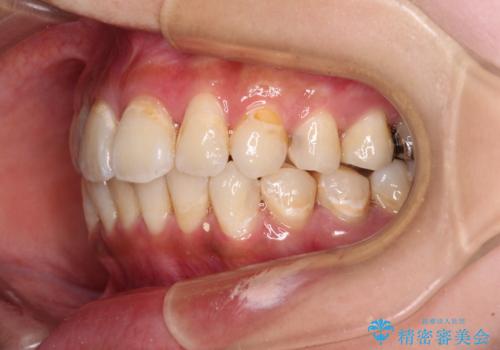

- 虫歯が多く、磨きにくい歯並びを改善したいとのことで来院された患者様です。

歯列は叢生が認められる程度でしたが、やや前突感があったので、少しでも口が閉じやすくなるように仕上げる方針としました。

神経を取り除かれている歯3本以外にも虫歯が認められたため、事前に処置を行い、インビザラインにて矯正治療を行うこととしました。

神経が取り除かれている歯は、クラウンによる補綴治療が必要であるため、矯正治療後にオールセラミッククラウンにて補綴治療を行うこととしました。

歯磨きしやすくなるとともに、飛び出していた前歯も引っ込めて整えることができました。